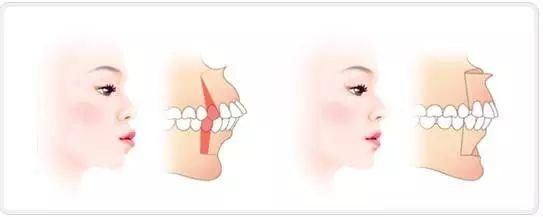

并且可能伴随着咬合不正(位置不对)的情况,此时需要采取的是复杂的双鄂手术,上颚(上颌骨)和下颚(下颌骨)同时截断,重新矫正到理想的位置上,从而使患者拥有正确的咬合状态和脸型。

▲双鄂手术方式示意图

除了能改善双鄂突出导致的凸嘴以外,撅下巴(地包天)、长脸、面部不对称、咬合不正等也是在治疗的范围之内的。

▲双鄂手术可以改善咬合不正

手术的目的不仅仅是将凸出的嘴向后推几毫米, 让脸变得自然,美丽,此外也是可以矫正牙齿咬合不正,让咀嚼、发音、吞咽功能恢复正常。